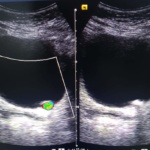

En las imágenes mostramos el caso de un lito (piedra) atorado en la porción más distal del ureter izquierdo cercano a su unión con la vejiga. El diagnóstico se realizó mediante ultrasonido.

Dra. Alejandra Espinoza

Especialista en Radiología.